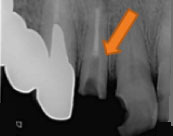

左下の奥歯に強い痛みを訴え来院。根管治療を施した。根管治療終了後、痛みはなくなり、炎症も認めないため、根管充填を施した。

左下の奥歯に強い痛みを訴え来院。根管治療を施した。根管治療終了後、痛みはなくなり、炎症も認めないため、根管充填を施した。

根管内に残っていた破折した金属リーマー。顕微鏡による的確に除去できた症例。

根管内に残っていた破折した金属リーマー。顕微鏡による的確に除去できた症例。